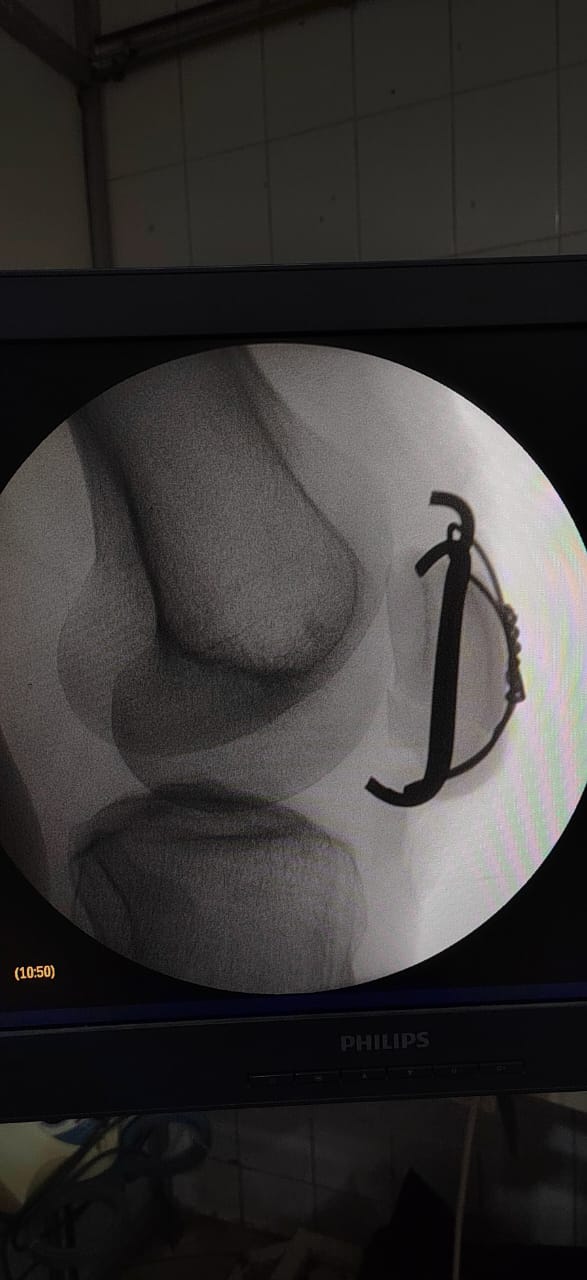

تركيب كويرات بالرضفة اليسرى لمريض.

وقد تمت العمليتان بدقة عالية وباستخدام أحدث التقنيات، وشارك فيهما فريق طبي وتمريضي وفني متكامل ضم:

الأطباء: د. شريف البيومي توفيق (عظام)، د. عيد السيد حسن (عظام)، د. ماهر فوزي كامل (تخدير).